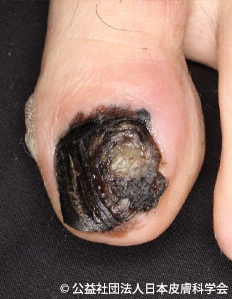

メラノーマ ほくろのがんQ2 - 皮膚科Q&A 公益社団法人日本皮膚科学会。

悪性黒色腫KOMPAS – 慶應義塾大学病院 医療・健康情報サイト。

悪性黒色腫 メラノーマ 皮膚腫瘍科がん研有明病院。